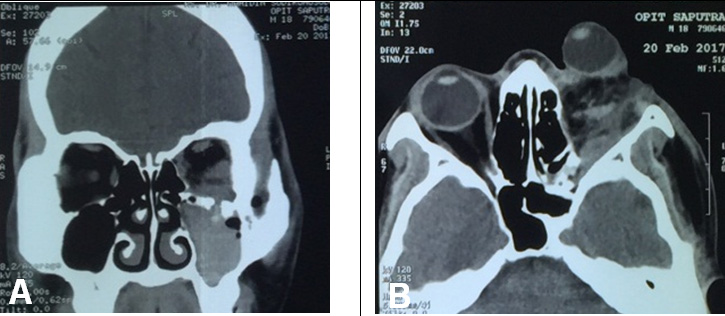

Clinically, the patient also had a blowout fracture and hematosinus in the left maxilary sinus (Figure 3). CT scan images also showed protrusion of the left globe suggestive of avulsion of the optic nerve (Figure 3). Intracranial structures were normal as well as the right eye that had 20/20 vision and no sign of trauma. The patient was hospitalized and intravenous antibiotic and corticosteroid were continued.

The fracture occur in the maxillary bone (inferior wall of the orbit) and combined with the bleeding in the orbital area, the blood entered the maxillary sinus making the appearance of hematosinus in the CT scan. The orbit is the bony cavity that contains the globe, extraocular muscles, nerves, fat and blood vessels [9]. This cavity consist of four walls; the roof, the floor, the lateral and medial wall, the weakest point being the lamina papyracea located in the posteromedial portion of the maxillary bone [9].